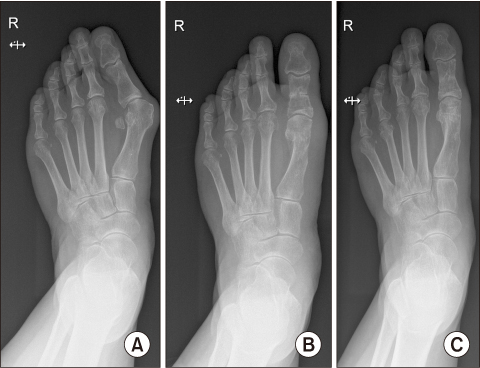

This study evaluated the clinical and radiological results after reinforcement of the weakened medial joint capsule using Internal Brace (Arthrex) for treating severe hallux valgus.

This study reviewed 56 cases of 50 patients that were followed-up postoperatively for at least 12 months, from September 2017 until August 2018. An extended distal chevron osteotomy combined with a distal soft-tissue release was performed by a single surgeon to treat severe hallux valgus. Internal Brace was applied in 12 cases (group A) who had weakened medial joint capsules, and capsulorrhaphy was performed in 44 cases (group B), and these two groups were compared postoperatively for the clinical and radiological results. The postoperative complications were also investigated.

No significant differences at 1-year follow-up on the Manchester-Oxford Foot Questionnaire and the patients' satisfaction scores were found between the two groups (p=0.905 and p=0.668, respectively). For the radiology, the changes of the values between before surgery and at 1-year follow-up according to the group showed no significant differences in the hallux valgus angle, intermetatarsal angle, and the hallux interphalangeal angle (p=0.986, p=0.516, p=0.754, respectively). Recurrence of hallux valgus was reported in two cases in group A, and in three cases in group B. Transfer metatarsalgia occurred in 4 cases in group B.

Based on these results, we recommend the capsule reinforcing technique using Internal Brace as a successful operative option for treating a weakened medial capsule in patients with severe hallux valgus.